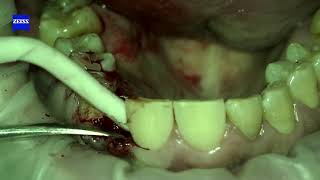

Временная Композитная Реставрация

346

0:55